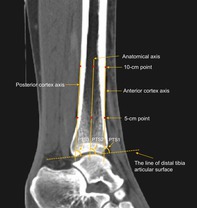

Methods: A retrospective analysis was conducted in healthy populations who underwent CT scans of the ankle joint. A total of 106 participants (53 males and 53 females) were included in our study. The three-dimensional model of the ankle joint was reconstructed by CT images, and the standard coronal and sagittal planes were produced using the anatomical coordinate system. The PTS was measured on different CT sagittal planes and virtual radiographs. All measurements were performed using three reference axes, including the anterior cortex axis, the anatomical axis, and the posterior cortex axis of the tibial shaft. Subgroup and correlation analyses were performed to investigate the effect of participants' demographic characteristics (the age, height, gender, and BMI) on the PTS. Statistical comparisons between two groups were performed using independent t-tests, while variations across sagittal planes and reference axes were analyzed through one-way analysis of variance.

Results: The mean values of PTS varied from 76.7° to 83.4° on different sagittal planes of CT images, and there was an increasing trend for PTS from the medial to lateral CT images. The mean values of PTS on the virtual radiograph were 81.6°, 82.3°, and 80.8° for the anterior cortex, anatomical, and posterior cortex axes, respectively. Significant differences in PTS measurements were found between CT images and virtual radiographs (p < 0.05). However, no differences were found while using different reference axes on PTS measurements (p < 0.05). Subgroup analysis showed females had a greater PTS than males, indicating a gender-based difference in the anatomy of the PTS.